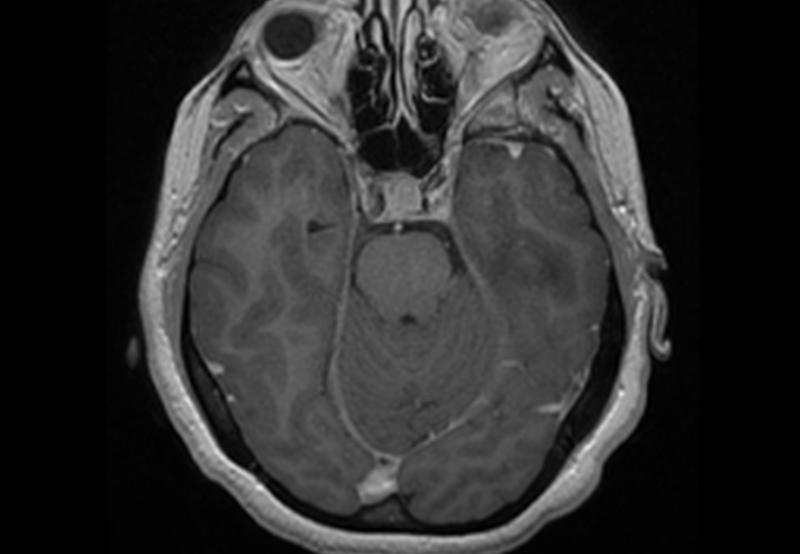

Los astrocitomas son tumores cerebrales que se originan de las células gliales y se dividen en 4 grados de acuerdo a la Organización Mundial de la Salud.

Los 2 primero grados corresponden a los astrocitomas de bajo grado, mientras que el 3er (Astrocitoma anaplásico) y 4to (Glioblastoma multiforme) grado corresponden a astrocitomas de alto grado.

El tratamiento siempre incluirá cirugía con el propósito de obtener muestra de tejido para ser enviada al experto en patología para que establezca el diagnóstico. Una vez obtenido el resultado definitivo con el grado de malignidad se canalizará si lo requiere a tratamiento complementario con quimioterapia (Temozolamida) y radioterpia.